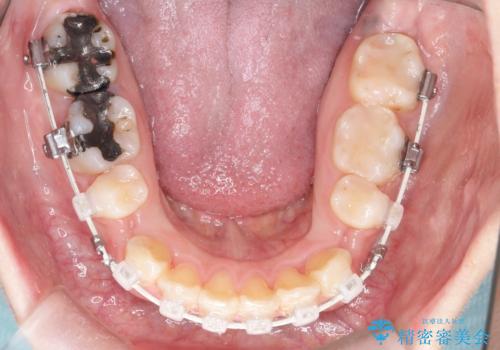

上下左右小臼歯を抜歯して審美装置で治療を行いました。

抜歯したスペースをきちんと下げることができるように、矯正用のアンカースクリューを用いて治療をしております。